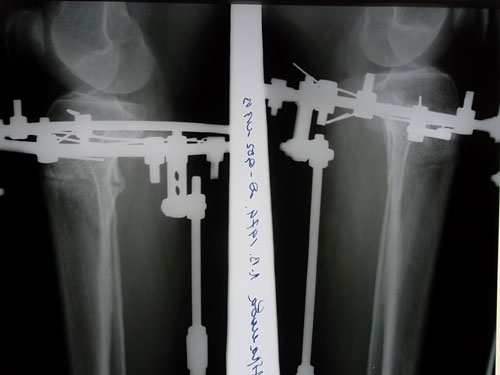

Рентгеновские снимки в день снятия аппаратов.

Дата операции 14.08.2012г.

Дата снятия аппаратов 15.11.2012г.

Срок лечения 90 дней.